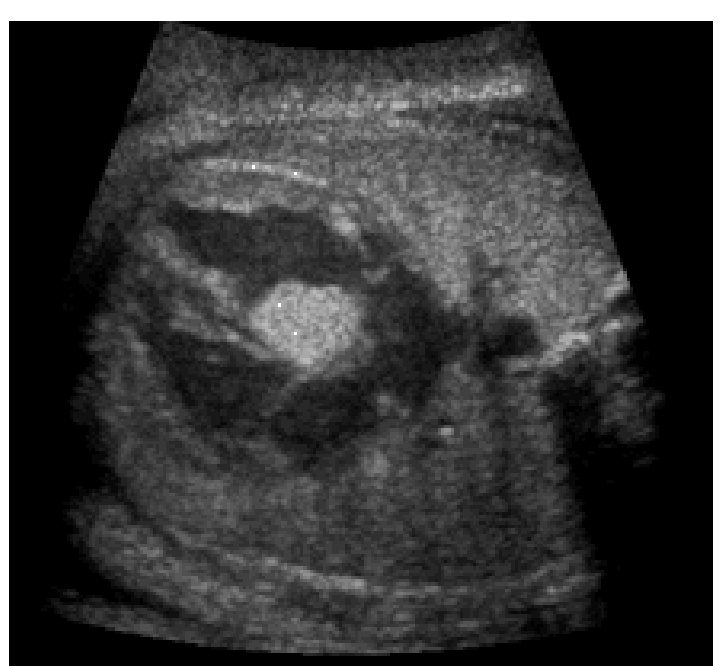

Fibroma, is a what tumors?

Single Intracardiac tumors

Fibroma, are found within where and are found within the what wall?

They are surrounded by what?

Do Fibromas regress?

Found within the ventricular septum and are found within the left or right ventricular wall

They are surrounded by myocardium

Fibromas do not regress

Fibroma

May influence the what system, cause what obstruction? and name 4 others things

May influence the conduction system, cause an outflow track obstruction, CHF, AV regurgitation or sudden death from an arrhythmia

(May need premature delivery and urgent surgery)